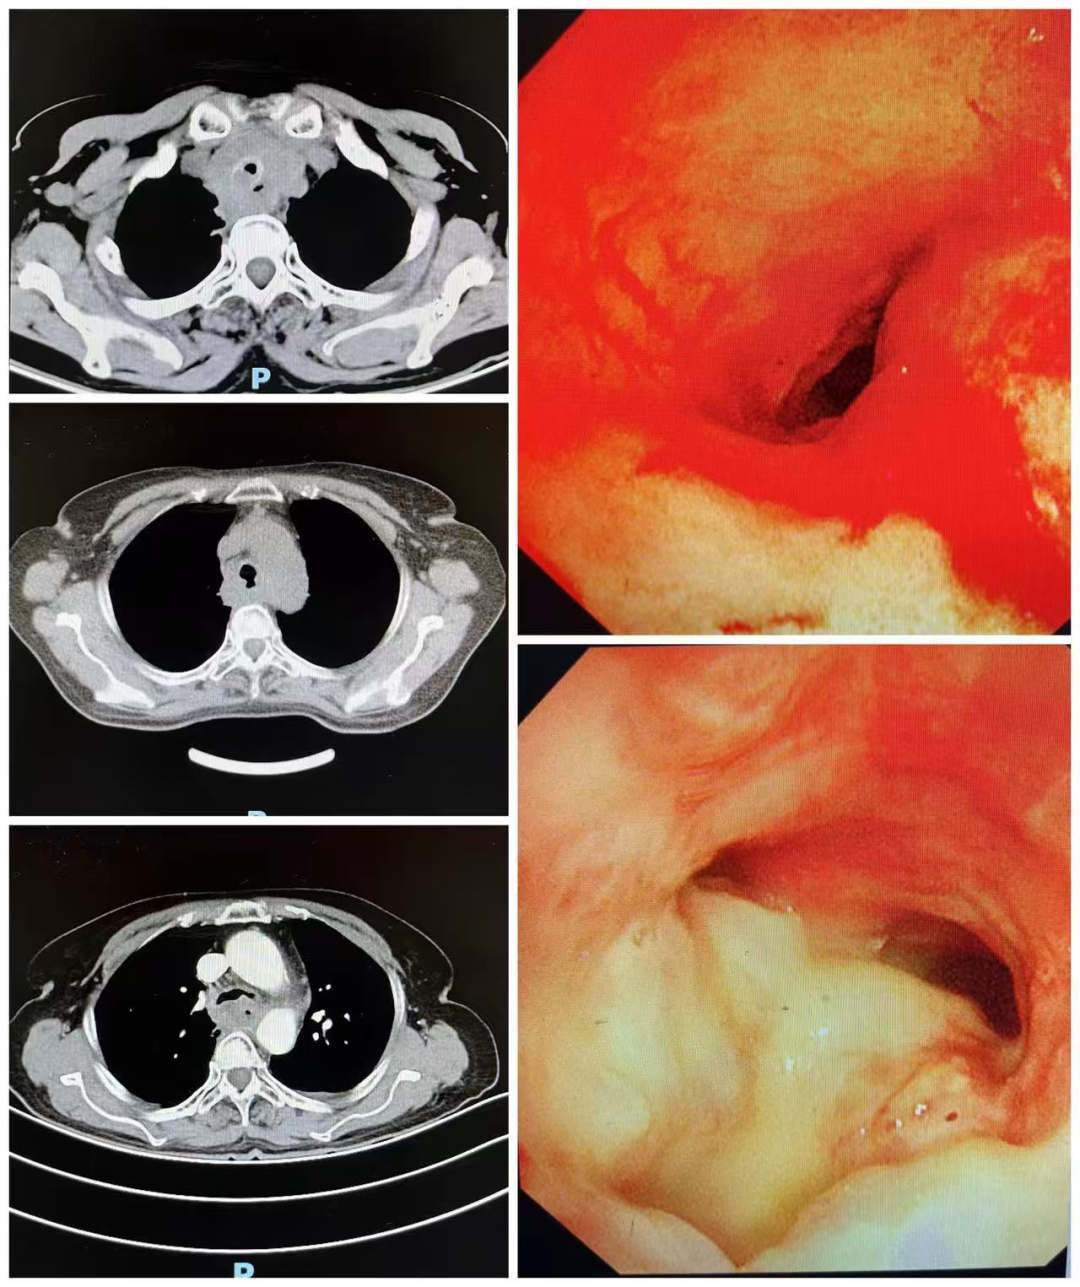

术前胸部CT及气管镜检查提示,患者大气道明显狭窄,狭窄处直径仅约6mm,长度约40mm,远低于正常人15–20mm的气管直径。此外,患者无法耐受缺氧,麻醉风险极高,手术难度大。面对这一复杂病情,肺病二科联合麻醉、医务部、内镜中心及重症医学科等多学科团队,全面评估患者情况,反复讨论并制定了周密的手术方案,全力保障患者安全。

本次接受手术的71岁女性患者,正是面临这样的危急情况。她因“胸闷、喘憋、咳痰一月余,加重伴发热1天”前来就诊。患者既往有食管恶性肿瘤病史,虽曾接受放化疗,但肿瘤仍在恶化,导致呼吸困难入院。进一步检查发现,患者气管严重狭窄,并存在气管食管瘘。由于气道狭窄,患者轻微活动即感憋喘,只能卧床;同时,食物经瘘口误入气管,引发大面积肺炎,痰液难以咳出,存在窒息及生命危险,急需手术干预。

患者术后胸部CT及镜下图片